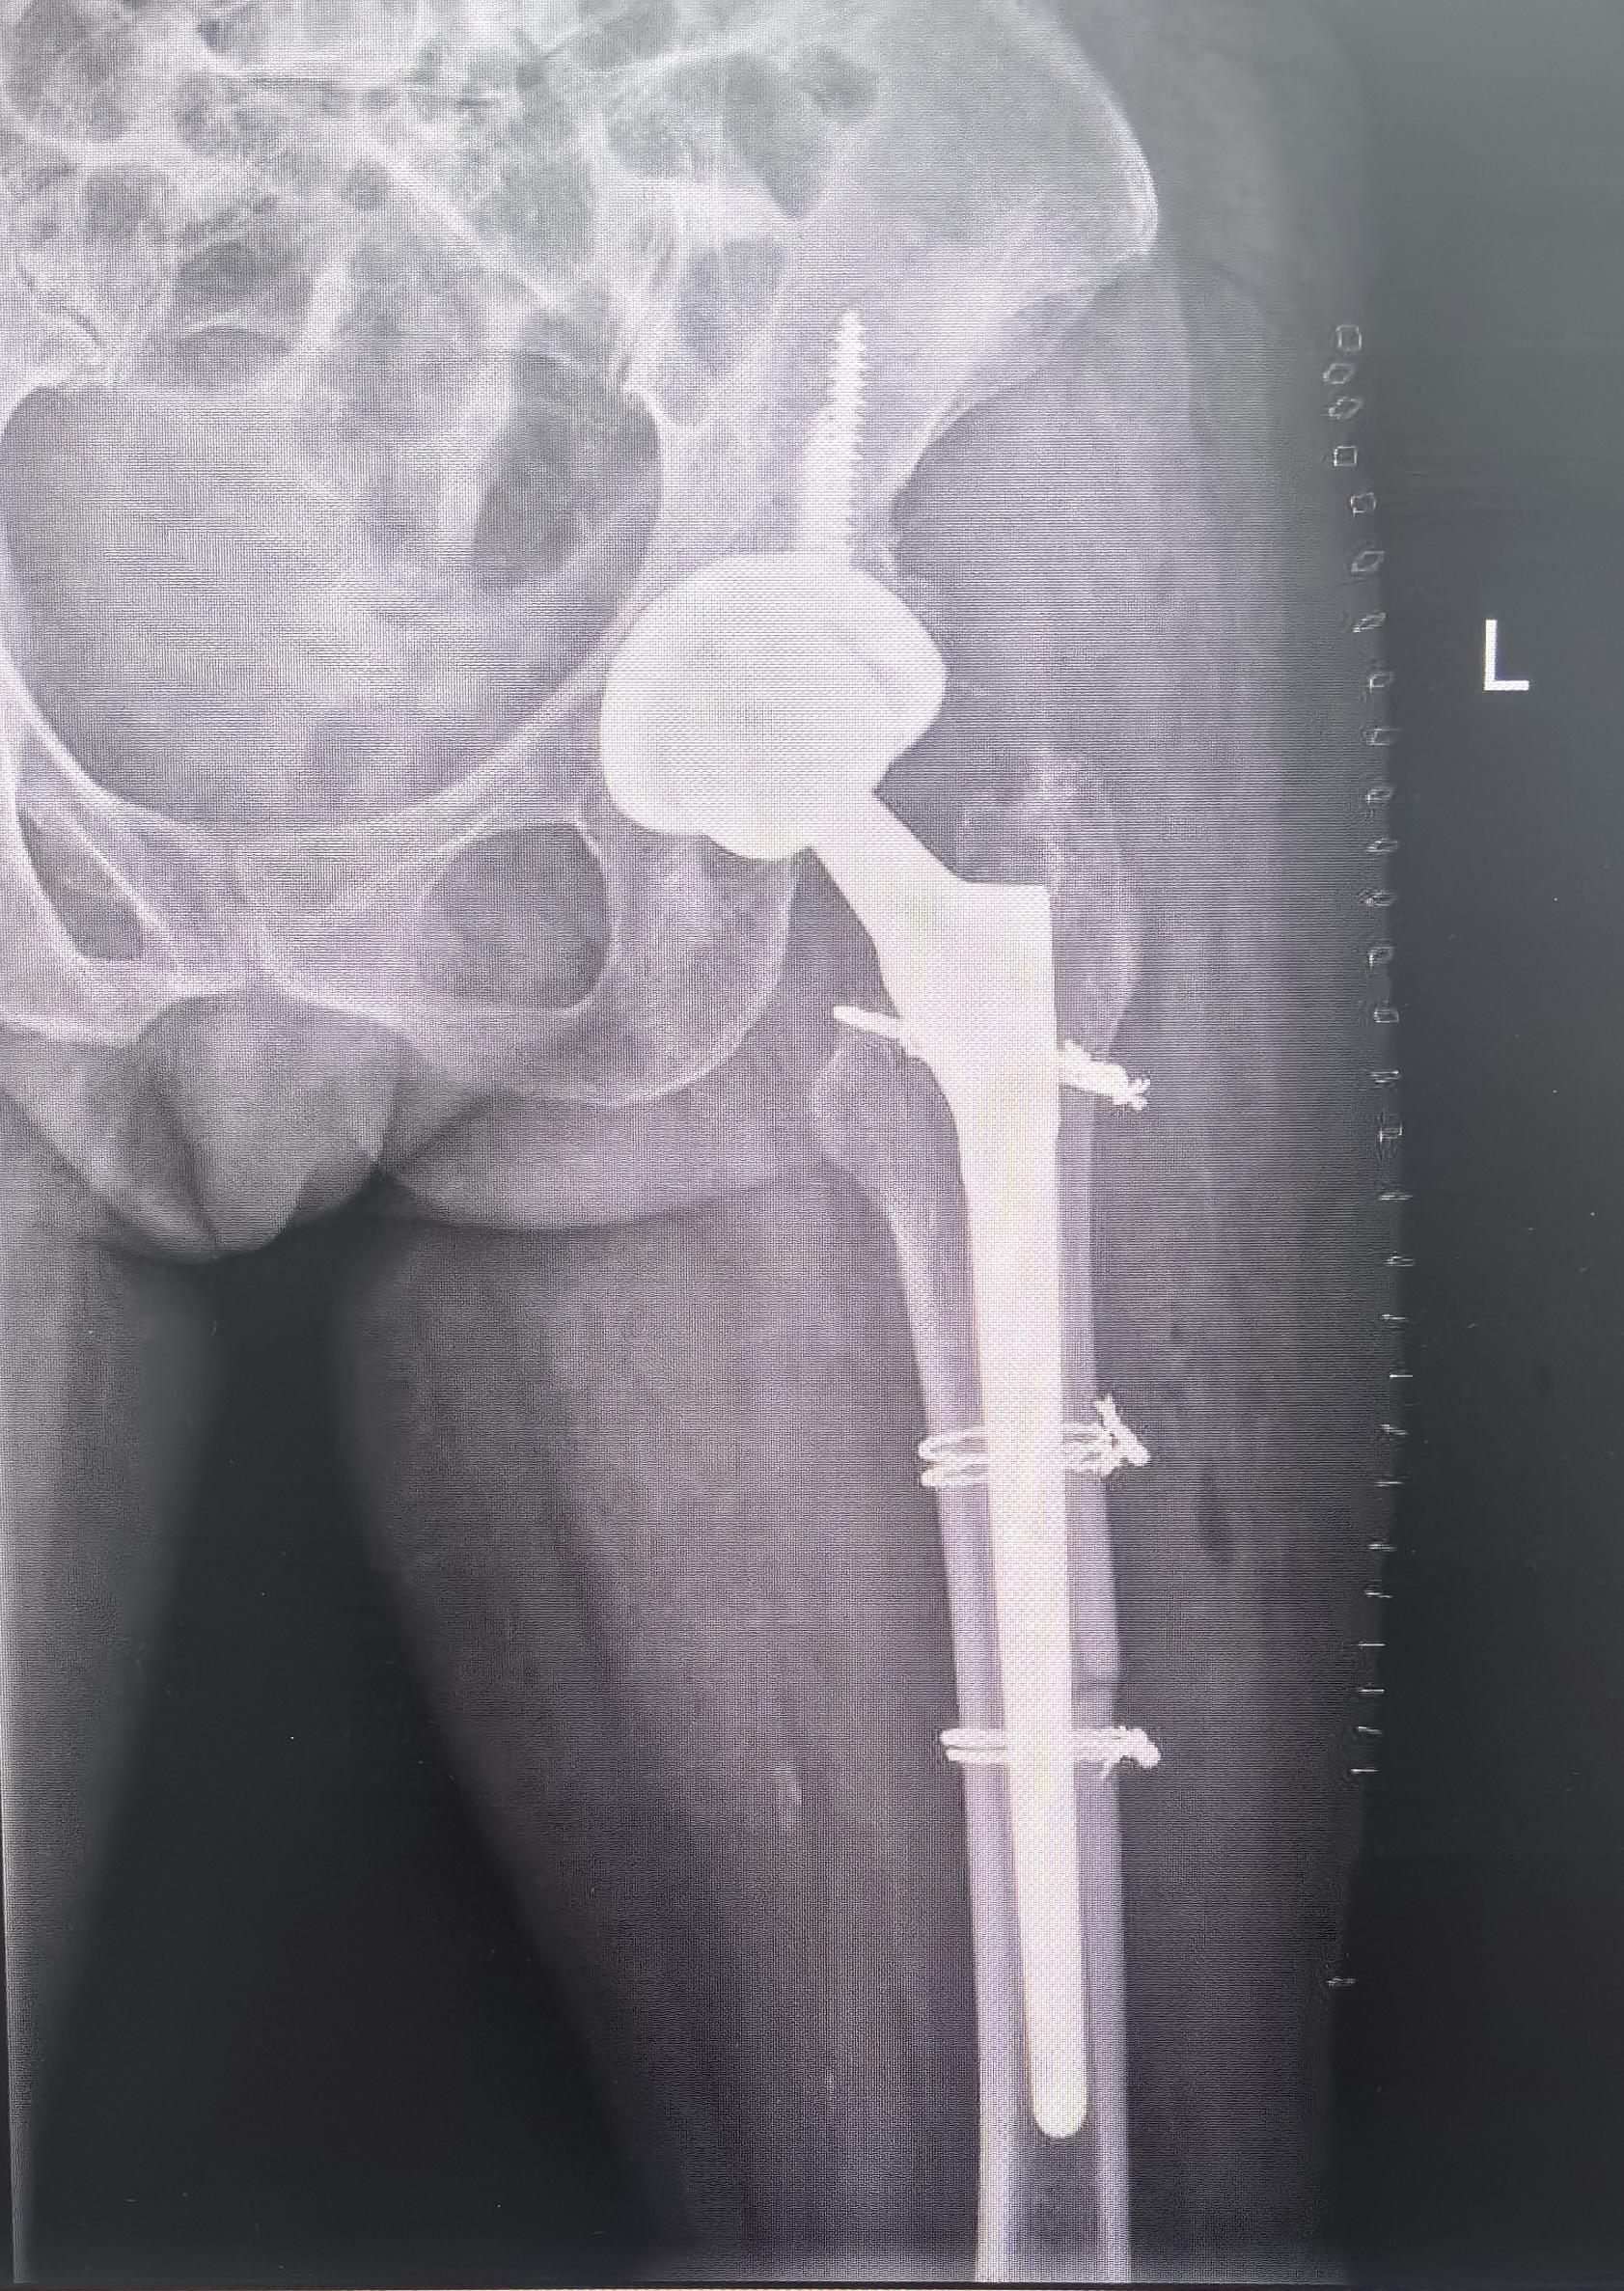

髋关节翻修。髋关节置换术后22年,假体磨损,骨溶解,无菌性松动,翻修术后再次恢复正常生活🌹